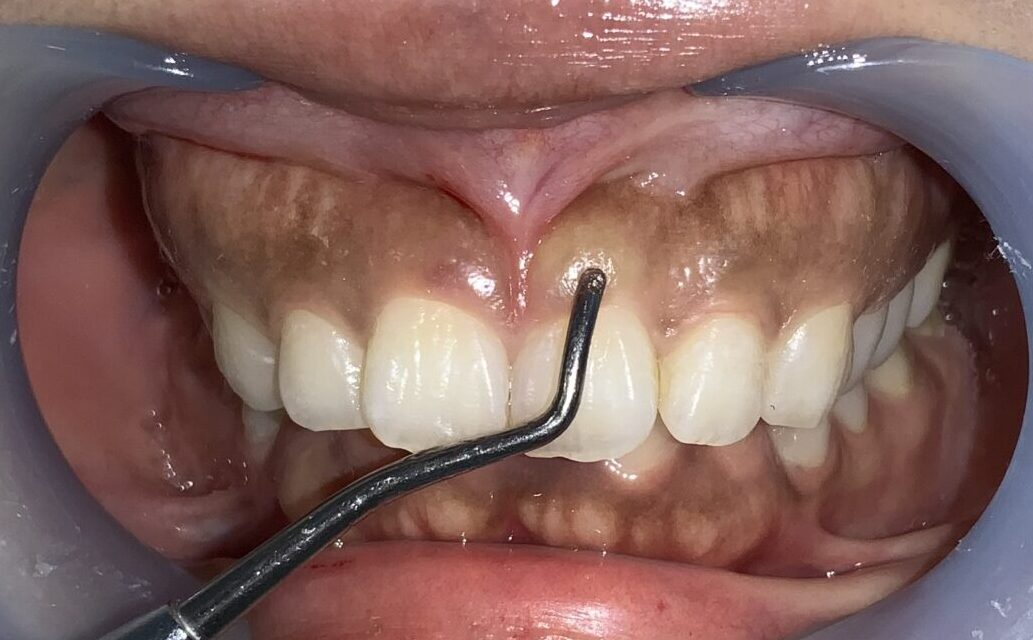

まずは手術前の状態です。

歯に歯ぐきがたくさんかぶっている状態です。

上の歯が下の歯を覆い被せてしまい、下の歯が全く見えない状態を過蓋咬合(かがいこうごう)と言います。

このような患者様は歯が歯ぐきに潜り込んでいる場合が多く、同時に歯槽骨が尖っていたり、ざらざらしていたり、歯槽骨までが歯を覆い被せていたりする場合がありますから、歯冠長延長術と同時に歯槽骨整形も一緒にしなければ、後戻りをしたり、綺麗に仕上がらない場合があります。